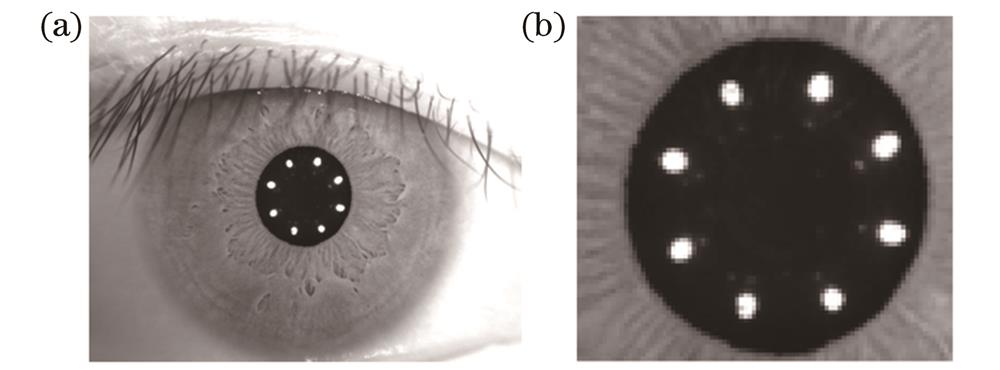

图 4. 采集的人眼图像与ROI图像。(a)人眼原图像;(b)瞳孔ROI图像

Fig. 4. Collected image of human eye and ROI image. (a) Original image of human eye; (b) ROI image of pupil

感兴趣区域提取前后的灰度分布如